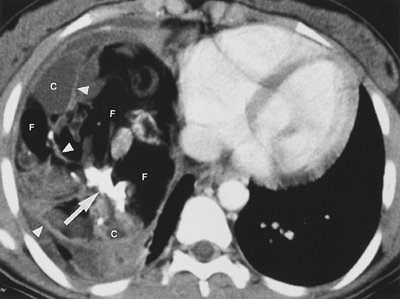

FIGURE 6-15. Benign teratoma. CT scan of a 16-year-old girl shows a large mass containing fat (F), cystic areas (C), and rudimentary "teeth" (arrow). Septations are present within the mass (arrowheads). At this windowing, fat appears similar in attenuation to air. Unequivocal fat within the mass confirms the diagnosis of teratoma. Note that large mediastinal masses can appear to fill an entire hemithorax.